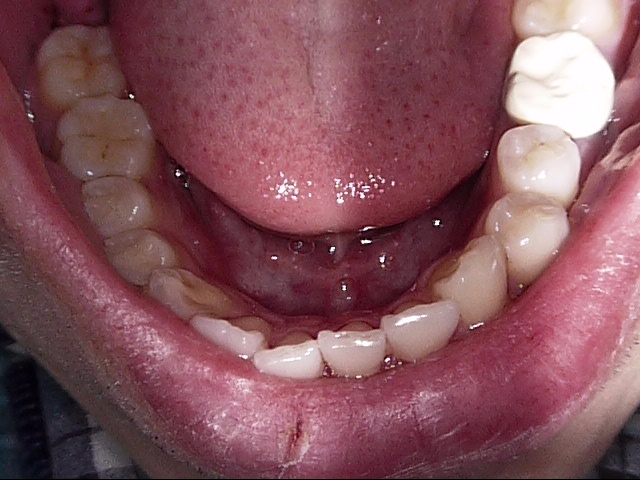

白い歯のなかでも保険適応のPEEK冠といって、割れにくい被せ物もあるのですが、色が真っ白になってしまうので、悪目立ちします。

PEEK冠の1例↓